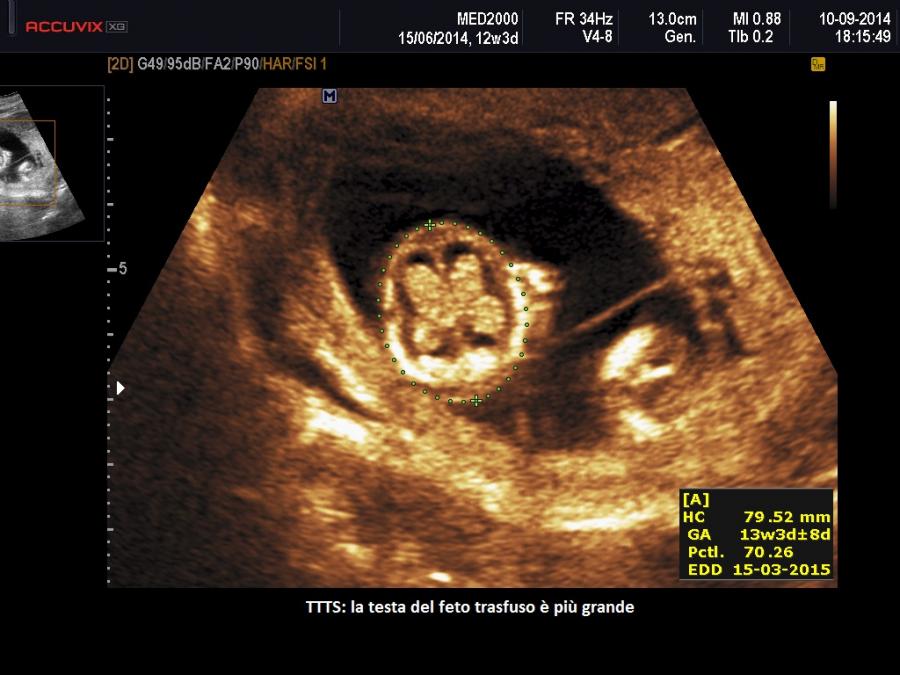

Quando il delicato equilibrio tra i vasi sanguigni dei due gemelli viene meno si verifica la malattia. La sindrome TTTS è caratterizzata dal passaggio anomalo di sangue e di sostanze vasoattive attraverso le anastomosi da un gemello (definito donatore) all’altro (definito ricevente). Lo squilibrio emodinamico che ne deriva comporta un aumento del volume di liquidi nel gemello ricevente con aumento del precarico dimostrato da un flusso venoso ombelicale più elevato (Yamamoto M. et al., 2007), che provoca aumento di volume delle camere cardiache con rilascio del peptide natriuretico atriale e cerebrale cui segue un aumento della diuresi e conseguente polidramnios (Van Mieghem T. et al, 2010; Habli M. et al, 2010). Inoltre aumenta la produzione di endotelina, un potente vasocostrittore, con conseguente ipertensione del ricevente ed ipertrofia cardiaca e rigurgito valvolare (Habli M. et al, 2010; Bajoria R. et al, 1999). Di converso nel gemello donatore si ha ipovolemia e successivamente una ridotta produzione di urina con conseguente oligoidramnios e riempimento vescicale minimo o assente. In risposta si verifica una sovraregolazione del sistema renina-angiotensina che passa al ricevente ipervolemico attraverso la circolazione condivisa amplificando l’ipertensione e la cardiomiopatia (Mahieu-Caputo D. et al, 2005; Galea P. et al, 2008).

La visualizzazione della vescica e la valutazione della flussimetria Doppler del cordone ombelicale e del dotto venoso in entrambi i feti permette di definire lo stadio di evoluzione della patologia che viene distinta in 5 stadi (Quintero R. et al, 1999):